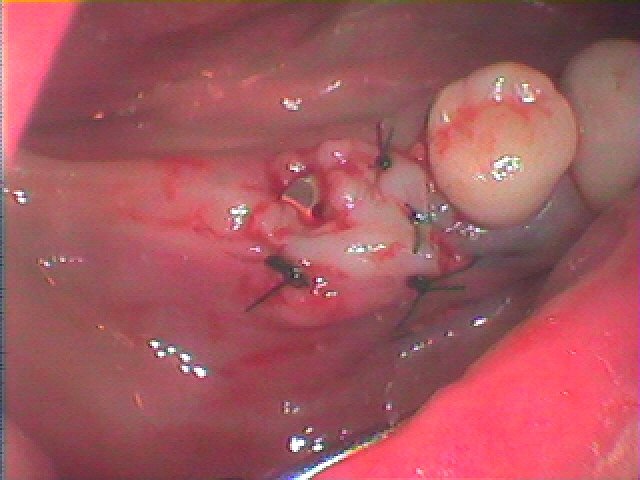

骨補填材を転入して縫合して終了となります